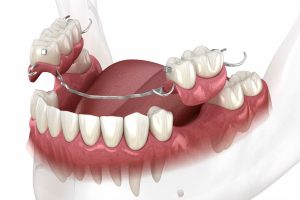

A flipper partial denture is a simple, affordable solution to restore missing teeth. Many people